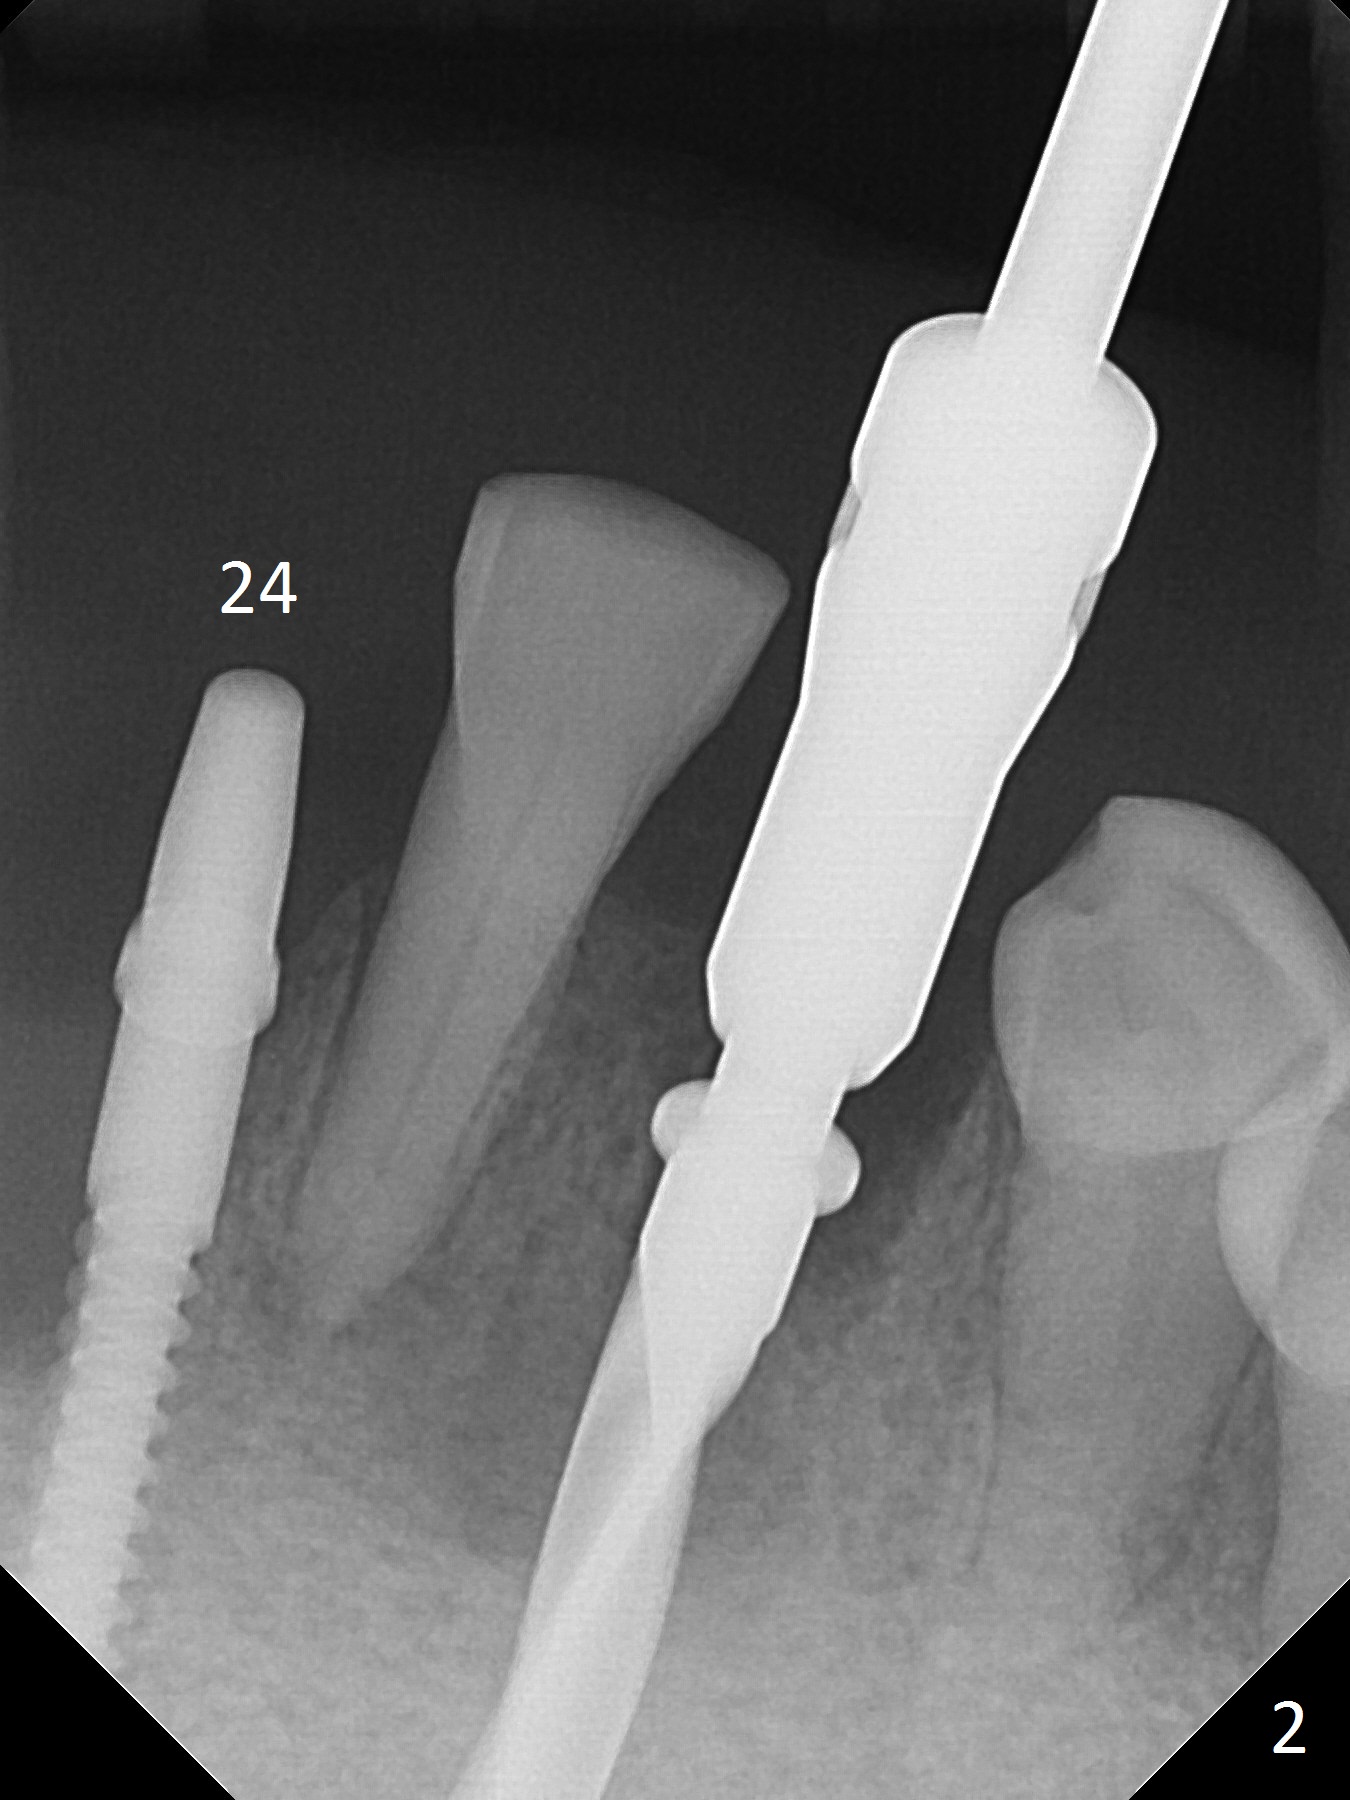

The depth of the osteotomy at #22 is 2-3 mm more than the expected implant length (Fig.2 with 2.7 mm drill in place). The implant at #22 (3.8x18 mm with insertion torque more than 50 Ncm) has clearance from the Incisive Canal and Mental Loop (Fig.3 red dashed line). Allograft with Osteogen is placed around the implants (Fig.4 *) in addition to Osteogen plug (cut in a thin layer) placed against the buccal wall of the socket at #22 (potential leakage). After suturing (Fig.5) and provisional cementation (Fig.6), periodontal dressing is applied (Fig.7). The implants seem to be ready for impression 4 months postop (Fig.8).